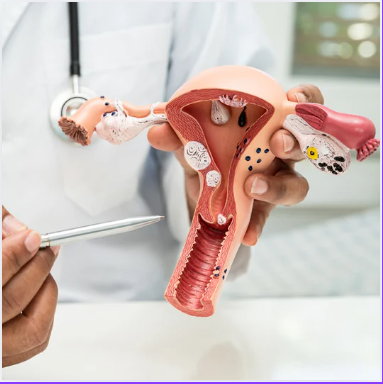

Gynecology